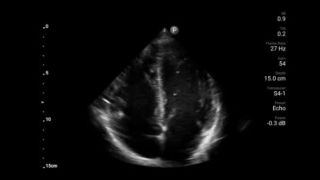

Exceptional ultrasound imaging

Lumify handheld ultrasound offers images that enhance diagnostic confidence.